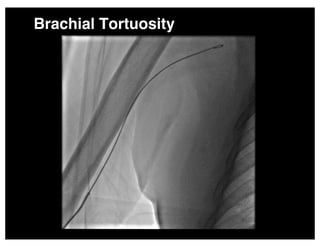

Brachial Tortuosity